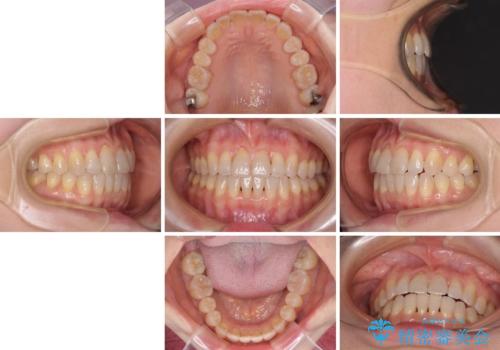

前歯の叢生と切端咬合 インビザラインによる矯正治療

上下前歯の先端同士が接触する切端咬合であったため、上顎は歯列を拡大し、下顎はIPR(歯と歯の間を削る)により叢生を解消しながら歯列を小さくすることとしました。

治療前から歯肉退縮が認められ、矯正治療により悪化する可能性が考えられたため、無理のない歯の移動と頻繁な経過観察を行いました。

切端咬合はスムーズに解消され、前歯の負担を軽減させることができました。